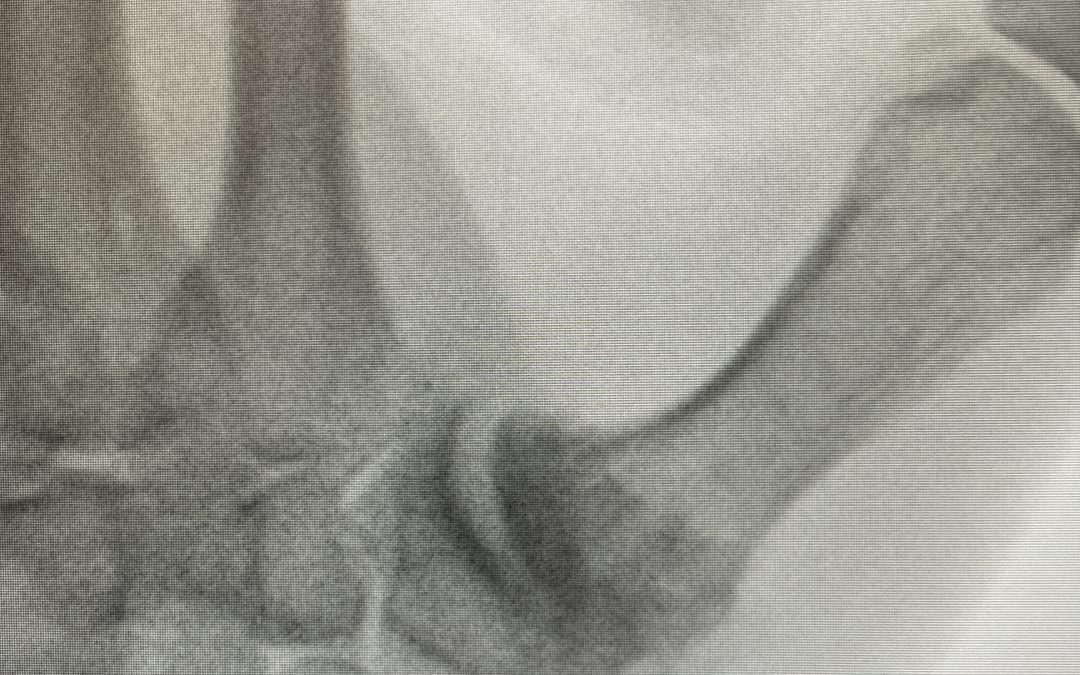

¿Qué es la Rizartrosis? Se denomina rizartrosis a la afección degenerativa que afecta la articulación trapecio-metacarpiana, ubicada en la base del pulgar. Se trata del 2º cuadro de artrosis más frecuente en la mano, tras la artrosis de articulaciones interfalángicas...